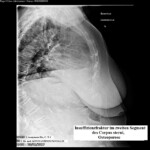

Σὲ ἀσθενεῖς πάσχοντες ἐξ ὀστεοπωρώσεως τὸ στέρνο εἶναι θέση ἐπιλογῆς καταγμάτων (κάταγμα ἀνεπαρκείας ἢ insuffizienzfraktur). Τὸ ἀπεικονιζόμενο στὴν εἰκ. Anonymous 81a περιστατικό ἀφορᾶ γυναῖκα 75 ἐτῶν, ὑπέρβαρη (93 Kgr, 147 cm ἀνάστημα), μὲ διαδοχική καὶ προϊοῦσα ἐπιδείνωση τῆς ὀστικῆς πυκνότητος (βαρειὰ ὀστεοπενία τὸ 2012-Anonymous 81b, ὀστεοπώρωση τὸ 2017-Anonymous 81c). Ἡ ἀσθενὴς ὑπέστη κάταγμα τοῦ 2ου τμήματος τοῦ σώματος τοῦ στέρνου, μὲ σημαντικὴ μετατόπιση τῶν κατεαγότων ὀστικῶν τμημάτων, κατὰ τὴν διάρκεια μιᾶς ἁπλῆς κινήσεως, ποὺ καθημερινὰ ἐκτελεῖ (ἐπίκυψη καὶ ἐπαφὴ τοῦ προσθίου τμήματος τοῦ θώρακος ἐπὶ μεταλλικῆς πόρτας τοποθετημένης ἐγκαρσίως ἐπὶ τοῦ ἐδάφους, προκειμένου νὰ δώσει τροφὴ στὰ ζωντανά της (διατηρεῖ λίγα πρόβατα καὶ κατσίκες). Καὶ σ’αὐτὴ τὴν κατηγορία καταγμάτων (ἀνεξαρτήτως μετατοπίσεως ἢ μὴ τῶν κατεαγότων ὀστικῶν τμημάτων) εἶναι ἐξαιρετικὰ δυσχερὴς ἡ διάγνωση -ἀκόμη καὶ μὲ ἀξονικὴ τομογραφία-. Λοξὲς ἢ ἐγκάρσιες περιγεγραμμένες ἑστίες προσλήψεως τοῦ ραδιοφαρμάκου στὸ σπινθηρογράφημα-σὲ συνδυασμὸ μὲ κλινικὴ συμπτωματολογία- θέτουν σοβαρὴ ὑπόνοια κατάγματος.